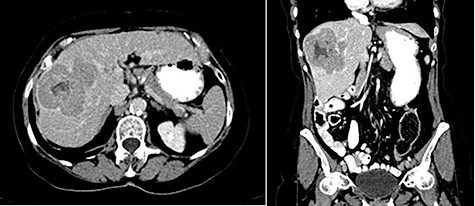

In 2018, the patient had a low dose chest CT for lung cancer screening, given her prior smoking history. The chest CT demonstrated a mass along the right hepatic dome. Triple-phase contrast-enhanced (ce) CT of the abdomen subsequently revealed a large multi-lobulated low-attenuation mass in the right hepatic lobe, predominantly involving Segments V and VIII and, to a lesser extent, Segments VI and VII, measuring 8.8 × 8.3 × 8.2 cm, and associated with a satellite lesion in Segment IVA, measuring 2.2 cm (Fig. 1). A PET CT was ordered and was negative for extrahepatic neoplastic disease.

Abdominal ceCT demonstrated an arterially enhancing mass with early washout characteristic of HCC; venous phase axial and coronal images are featured.